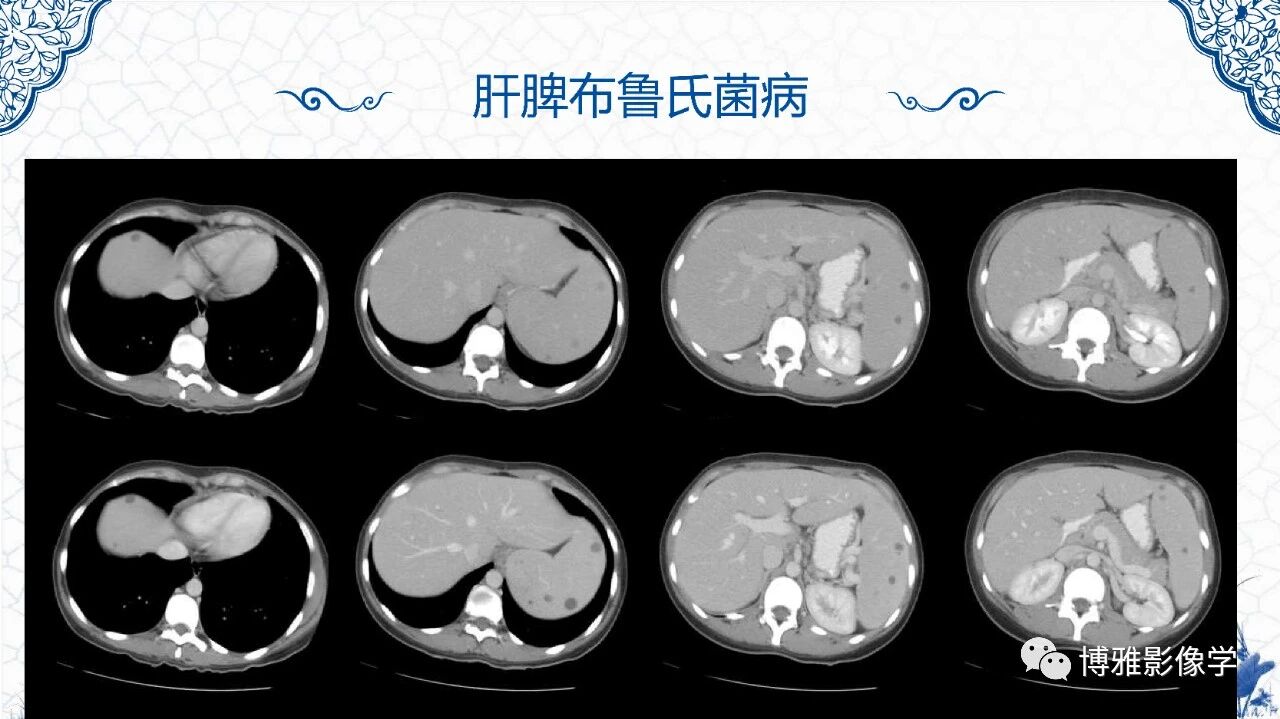

脾脏非肿瘤影像诊断